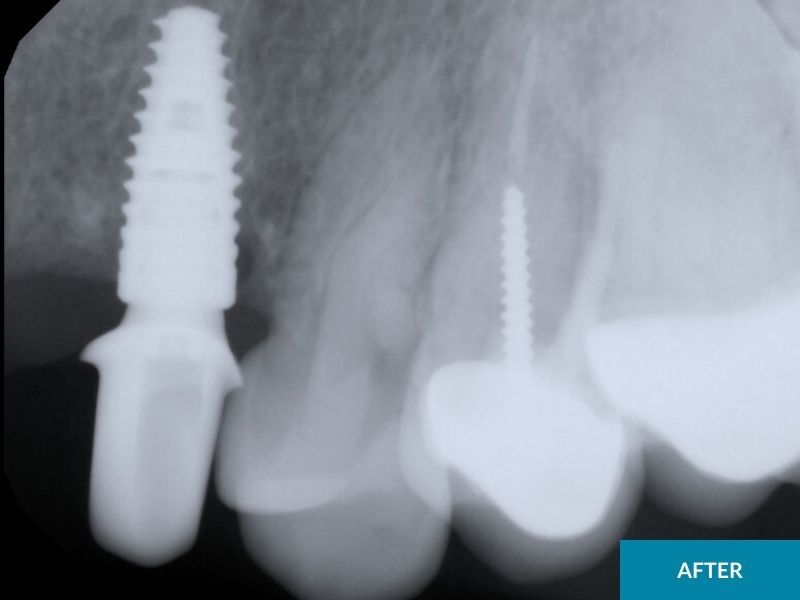

Placing dental implants and then putting a cap on it is a great way to replace a missing tooth if you do not want to put caps on the teeth adjacent to the missing tooth, or if there aren’t enough strong teeth to support a fixed bridge near the missing tooth. This is especially true if the adjacent teeth are perfectly healthy, straight, decay free-teeth and the patient would rather avoid capping them.